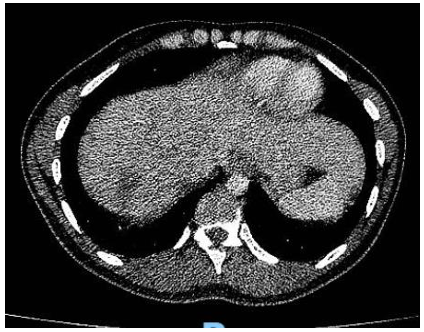

Debido a este hallazgo, con sospecha de enfermedad trofoblástica gestacional maligna se decide solicitar estudios de extensión TC tórax(Imagen 1), abdomen y pelvis(Imagen 2) en los cuales se evidencian múltiples lesiones focales en ambos campos pulmonares, destacándose por su tamaño, aquella ubicada en región anterior del campo pulmonar derecho, comprometiendo lóbulo medio y lóbulo superior, de 25mm. Sugieren valorar secundarismo. El hígado presenta múltiples lesiones focales heterogéneas, con realce con el contraste endovenoso, la mayor a nivel del segmento Vll, de 60mm, vinculables a secundarismo en primer término. Bazo de tamaño conservado, con lesión de semejantes características a las descritas en hígado, de 42mm, asimismo sugerente de secundarismo. Útero ausente en relación a los cambios descritos. Se observan aparentes engrosamientos nodulares a nivel del lecho quirúrgico, que realzan tras la administración de contraste EV y sugieren la presencia de implantes.

Imagen 2. TC abdomen (corte a nivel superior) al diagnóstico

Al mes de iniciado el tratamiento se realiza primer control con subunidad BHCG con un resultado de 202 mU/ml y al finalizar el mismo se encuentra un resultado de 3 mU/ml, una vez alcanzado este valor se realiza el mantenimiento con mismo esquema quimioterápico durante 1 mes, y se repite el dosaje de BHCG con un valor de 1 mU/ml. Además se solicitaron nuevos estudios por imágenes en base a las recomendaciones: TC tórax(Imagen 4), abdomen y pelvis(Imagen 5), y RMN de cerebro(Imagen 6) (no pudiéndose solicitar PET-TC debido a falta de cobertura por la obra social), en los mismos se encontró marcada disminución de tamaño de las imágenes nodulares en ambos campos pulmonares, imágenes focales hepáticas hipovasculares, correspondientes a imágenes secuelares e hipodensidad subcapsular esplénica de aspecto isquémico secuelar. En la RMN se informa alteración de la señal temporo-occipital izquierda de aspecto secuelar, probablemente en relación a restos de hemosiderina.

Imagen 5. TC abdomen (corte a nivel superior) post-tto